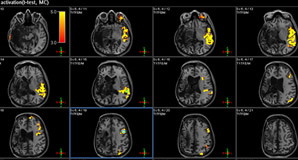

Interpretación de Estudios de Resonancia Magnética

La lectura de estudios de Resonancia Magnética es realizada por profesionales sub-especializados que garantizan alta calidad en su interpretación, t...